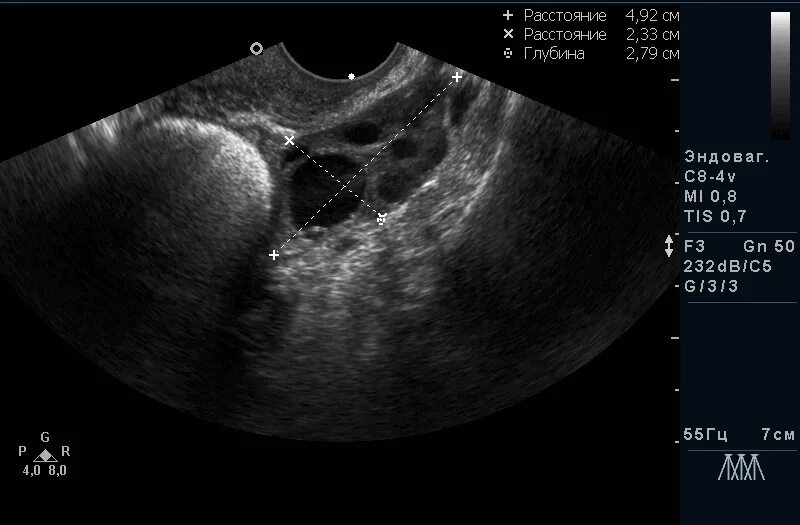

Какой размер доминантного фолликула